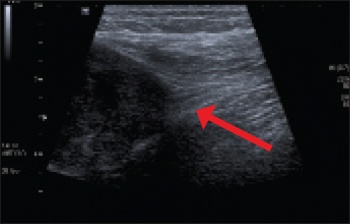

In addition to detection during routine screening, a cancer may be diagnosed incidentally while performing the investigation for another clinical presentation. In many cases imaging is performed to confirm the suspicion in patients with a clinically apparent cancer. A cancer may be detected with plain radiographs, ultrasound, mammography, CT or magnetic resonance imaging (MRI [see Figures 2 and 3]). Imaging provides details on the location of a cancer, the extent of disease and the presence of local or distant complications.

Figure 2. Ultrasound of solid mass in the posterior aspect of the thigh in continuity with the sciatic nerve, consistent with a peripheral nerve sheath tumour (PNST)

Figure 2. Ultrasound of solid mass in the posterior aspect of the thigh in continuity with the sciatic nerve, consistent with a peripheral nerve sheath tumour (PNST) (click to enlarge)